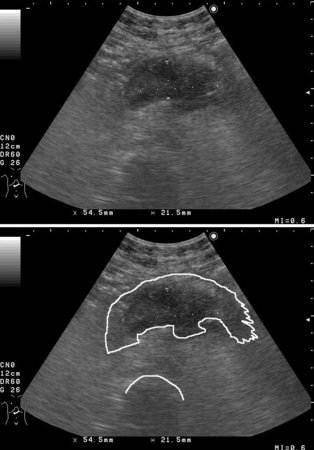

Опухоль тела панкреас. Pancreatic body tumor.

38-летняя женщина с болями в животе с иррадиацией в спину.

На КТ (без контрастирования - 2000 год) патологии не выявлено.